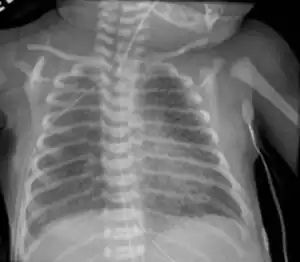

Infant respiratory distress syndrome most commonly occurs in less than six hours after birth in about 1% of all births in the United States.[9] The main risk factor is prematurity with the likelihood of it occurring going up to 71% in infants under 750g.[19] Other risk factors include infant of a diabetic mother (IDM), method of delivery, fetal asphyxia, genetics, prolonged rupture of membranes (PROM), maternal toxemia, chorioamnionitis, and male sex. The widely accepted pathophysiology of respiratory distress syndrome is it caused by insufficient surfactant production and immature lung and vascular development. The lack of surfactant makes the lungs atelectatic causing a ventilation to perfusion mismatch, lowered compliance, and increased air resistance. This causes hypoxia and respiratory acidosis which can lead to pulmonary hypertension. It has a ground glass appearance on an x-ray. Symptoms can include tachypnea, nasal flaring, paradoxical chest movement, grunting, and subcostal retractions.[9]

Meconium Aspiration Syndrome occurs in full term or post-term infants who aspirate meconium. Risk factors include a diabetic mother, fetal hypoxia, precipitous delivery, and maternal high blood pressure.[21] Its diagnosis is based on meconium stained amniotic fluid at delivery and staining on the skin, nails, and umbilical cord. Aspiration can cause airway obstruction, air-trapping, pneumonia, lung inflammation, and inactivated surfactant. It presents as patchy atelectasis and hyperinflation on an x-ray with a pneumothorax of pneumomediastinum also possible.[9]

Transient Tachypnea of the Newborn is caused by the retention of alveolar fluid in the lungs. It commonly occurs in infants who are delivered via caesarean section without the onset of labor because absorption of amniotic fluid in the lungs has not yet commenced. Other risk factors are male sex, macrosomia, multiple gestations, and maternal asthma. It usually presents with tachypnea and increased work of breathing. On an x-ray diffuse infiltrates, interlobar fissures, and sometimes pleural effusions can be seen. It is a diagnosis of exclusion because of its similarity to other diseases and frequently CPAP is used to help push the lung fluid into the pulmonary vasculature.[9][24]

Pulmonary interstitial emphysema is the condition of air escaping overdistended alveoli into the pulmonary interstitium. It is a rare disease that occurs most often in premature infants, even though it is possible to appear in adults.[25] It often presents as a slow deterioration with the need for increased ventilatory support. Chest x-ray is the standard for diagnosis where it is seen as linear or cystic translucencies extending to the edges of the lungs.[9]